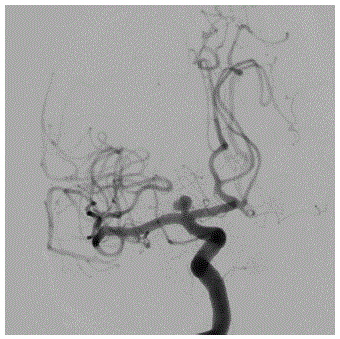

Assinale a alternativa que corresponde à CORRETA topografia do aneurisma cerebral na angiografia abaixo.